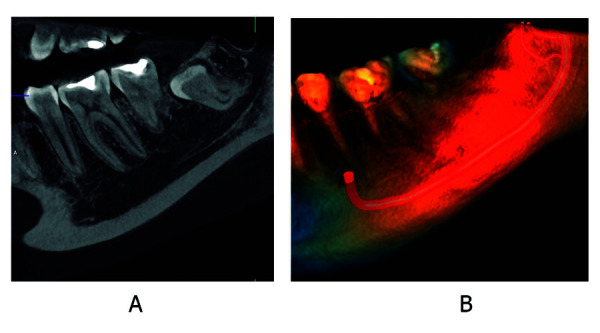

Abstract Image